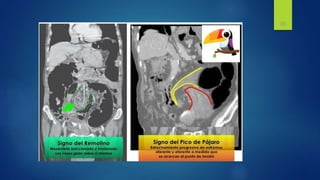

 TOMOGRAFIA

Sensibilidad 80-90%

Especificidad 70-90%

Proporciona datos de :

Obstrucción en asa cerrada y estrangulamiento

Lugar y causa de obstrucción

Hallazgos

• Zona de transición discreta

con dilatación proximal del

instestino delgado

• Descompresion distal del

intestino

• Contraste luminal que no va

mas alla de la zona de

transición

• Colon con poco gas o liquido